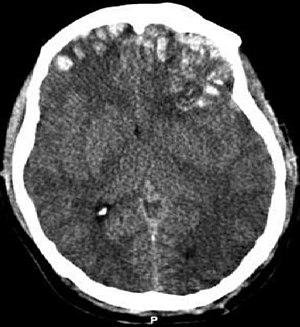

| CT scan showing cerebral contusions, hemorrhage within the hemispheres, and subdural hematoma. There is also displaced skull fracture of left transverse parietal and temporal bones.[2] | |

Hematomas, also focal lesions, are collections of blood in or around the brain that can result from hemorrhage.[24] Intracerebral hemorrhage, with bleeding in the brain tissue itself, is an intra-axial lesion. Extra-axial lesions include epidural hematoma, subdural hematoma, subarachnoid hemorrhage, and intraventricular hemorrhage.[105] Epidural hematoma involves bleeding into the area between the skull and the dura mater, the outermost of the three membranes surrounding the brain.[24] In subdural hematoma, bleeding occurs between the dura and the arachnoid mater.[32] Subarachnoid hemorrhage involves bleeding into the space between the arachnoid membrane and the pia mater.[32] Intraventricular hemorrhage occurs when there is bleeding in the ventricles.[105]